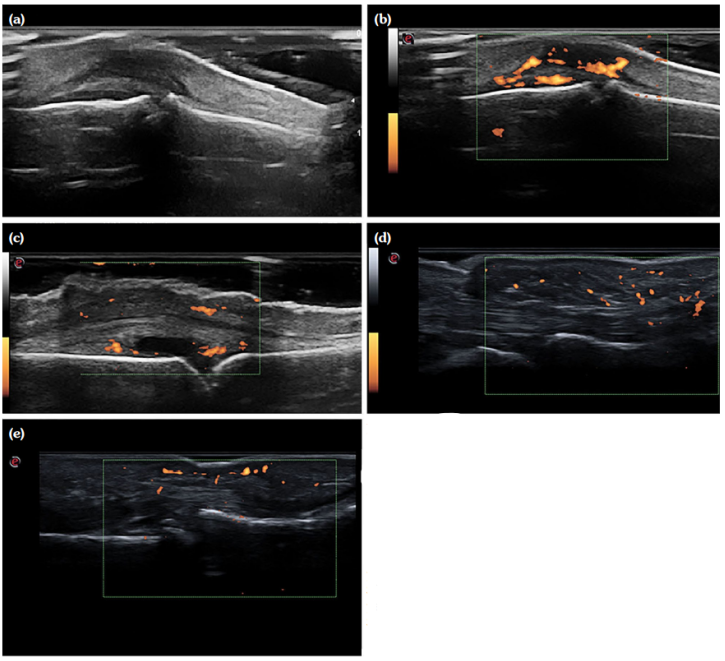

The palmar scan of the second MCP joint revealed a significantly higher incidence of tenosynovitis and pseudotenosynovitis in PsA patients (p<0.001), whereas the third MCP joint showed that pseudotenosynovits was significantly more prevalent in the PsA group (Table 2; Figure 1).

In our study, PsA patients were found to have a significantly higher incidence of flexor tenosynovitis and pseudotenosynovitis of the finger flexor tendon at the level of the second and third MCP joints. It is important from clinical point of view that patient-reported pain in PsA was found to correlate with extra-articular inflammation, predominantly flexor tenosynovitis, and soft tissue edema (pseudotenosynovitis),[42,43] whereas joint synovitis does not appear to cause pain in PsA, compared to RA, where joint pain is caused by joint synovitis, particularly if PD is positive. Only two studies of RA patients evaluating the correlation between USG-detected synovitis and joint symptoms found that joint tenderness on palpation does not correlate with the detection of joint synovitis by grey scale and PD USG.[27,44] To summarize, a patient reporting pain in the small joints of the hands should be screened for extrasynovial abnormalities and presence of mini-enthesitis, even in the absence of joint synovitis.

Data exists that finger flexor tenosynovitis is more prevalent in PsA.[35,45] Our study found a higher prevalence of flexor tenosynovitis in PsA than the one reported by Tinazzi et al.[45] (65% vs. 38%). A specific finding of PsA is the pseudotenosynovitis of the flexor tendon, described by some authors as STE around the finger flexor tendon, exhibiting a positive PD signal.[20] More than half of the PsA patients in our study demonstrated pseudotenosynovitis of the flexor tendon, a higher prevalence than that reported by Tinazzi et al.[45] (30%) and Zabotti et al.[22] (42.3%). An interesting fact is that STE is an even more common USG finding in the fingers with dactylitis, with a reported prevalence of 75 to 91% in hand dactylitis cases.[46] Felbo et al.[47] also found that STE is more common than flexor tenosynovitis and joint synovitis in dactylitis.